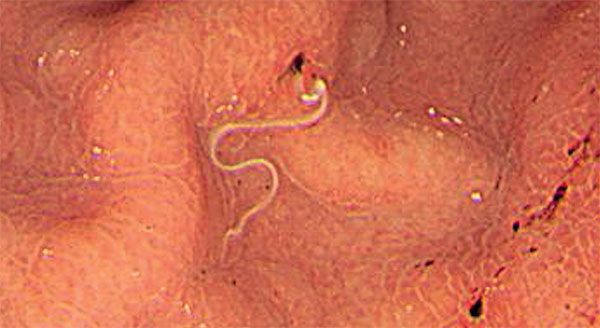

The Disgusting Thing More and More People Have Been ...

The Disgusting Thing More and More People Have Been ... from www.menshealth.com.au